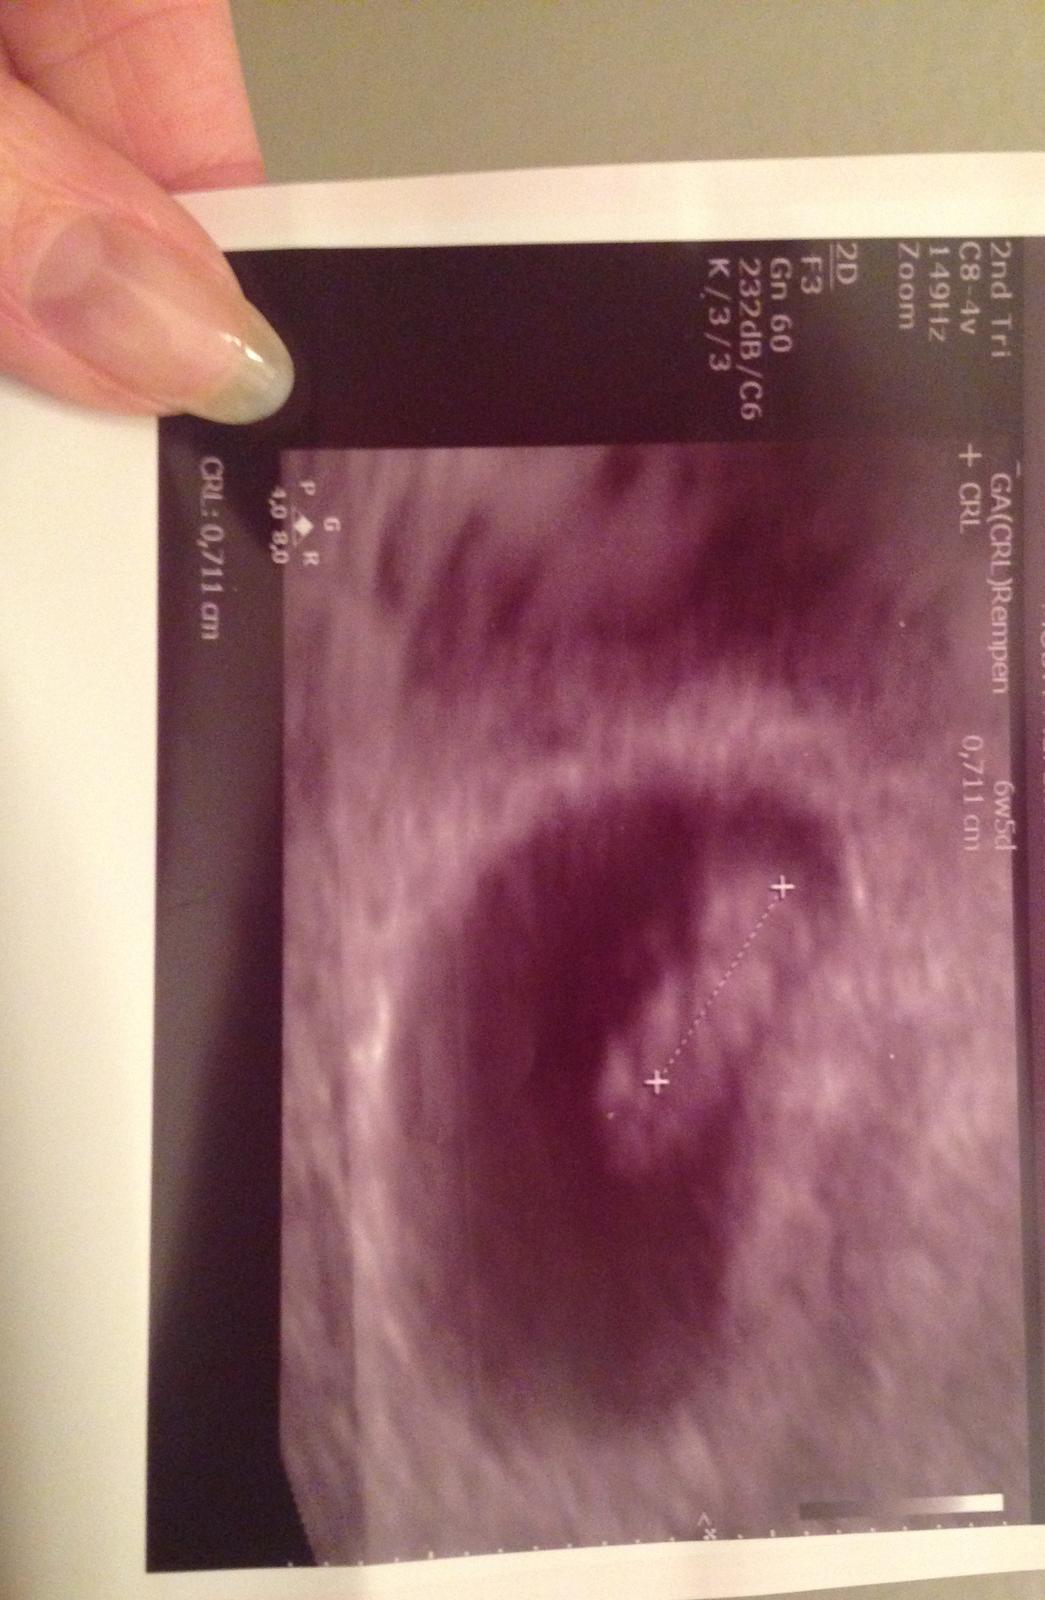

@miriamn76 @karmela @luta13 uz som vyplakana maminka najstastensia pod tymto svetom ❤️

mame 7mm , a srdienko nam krasne bilo💓,skackalo na tom monitore odusu ,moj bobik ...

vies ,ze tt ni neviem nevyjdril s dr. le podla kalkulcky som 6tt+6

ale podla mna len 6tt+2 kedze ja mam ovulku neskor

ale ked uz je srdienko to je pre mna najviac 💞